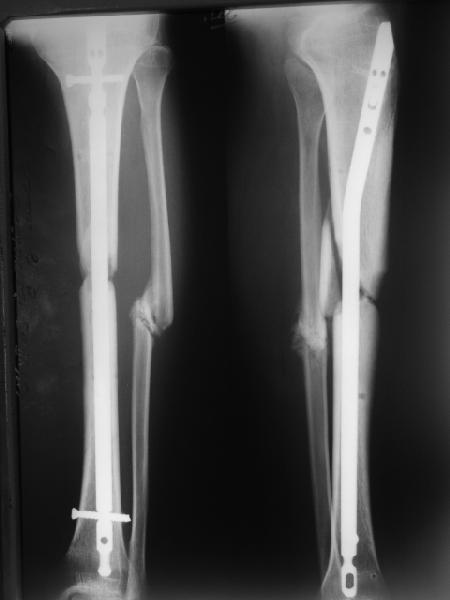

Вот пример, тоже открытый перелом, первичный дефект, пробыл в аппарате 5 мес. Титановый гвоздь,  сразу динамический, без покрытия. Больше не делали ничего.

Имя     : get_image3.jpg

Тип     : image/jpg

Размер  : 16205 байтов

Описание: отсутствует

Url     : http://weborto.net:8080/pipermail/ortho/attachments/20111023/02514467/attachment-0005.jpg